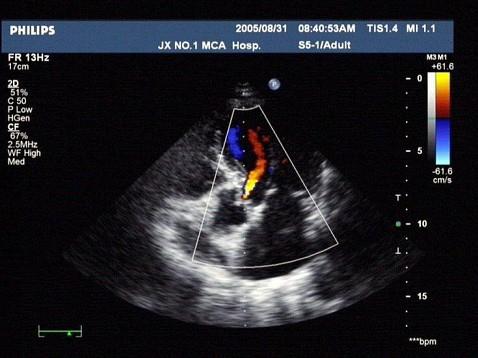

问题 如图,初步超声诊断为?(?)

选项 A.二尖瓣返流 B.三尖瓣返流 C.主动脉瓣返流 D.肺动脉瓣返流 E.主动脉瓣狭窄

答案 C